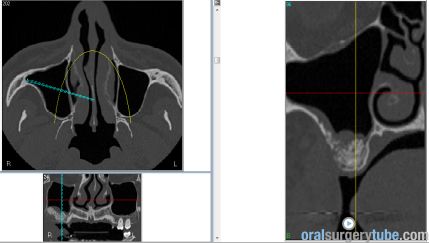

Con este comentario haremos una pausa en el caso hasta que llegue la colocación de los implantes. Por el momento, está todo solucionado. No hay sintomatología alguna, y lo más importante, en TAC realizado el martes 31.07.2018, podemos ver que el seno ha drenado por completo y está aireado. Hasta nuevo aviso, suspendemos todo tipo de medicación. Subimos imágenes del último TAC donde podemos apreciar que hemos perdido algo de xenoinjerto, pero la zona de menor altura aún tiene 10 mm. Podemos ver en una de las imágenes la zona de la ventana por donde el seno drenaba. Esperaremos el tiempo reglamentario para poder reevaluar si el xenoinjerto sigue siendo viable. Ha sido un gran placer contar con este equipo y poder aportar un grano de arena a solucionar complicaciones quirúrgicas.

Continúo con el seguimiento que vamos dando a este paciente: Visitado el miércoles 11.07.2018. Hay ausencia total de sintmatología. Retiramos el drenaje, hacemos Prueba de Valsalva positiva, pero sale aire y un poco de sangre. Dejamos cicatrizar por segunda intención. Pedimos continuar la medicación antibiótica y solicitamos un TAC. El seno maxilar está ocupado como vemos en la imagen, pero el biomaterial está contenido en la zona injertada: no existe ningún gránulo de xenoinjerto dentro del seno. La apófisis mastoidea está aireada.